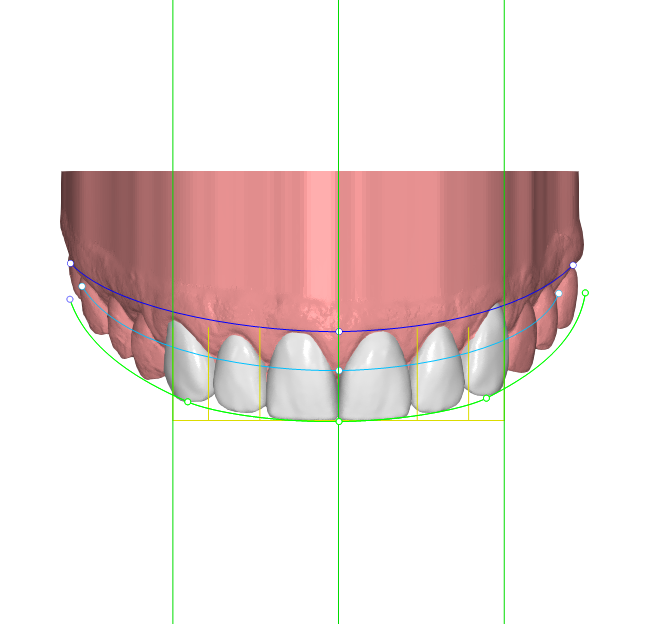

Paciente joven que acababa de finalizar su tratamiento de ortodoncia. Aunque estaba satisfecho con el resultado general, no se sentía cómodo con las troneras incisales que habían quedado entre los laterales y los caninos. Buscaba una solución rápida, estética y mínimamente invasiva

Desde Elevantia Solutions propusimos un Injectable Composite Design con carillas únicamente en esas piezas, para cerrar los espacios sin necesidad de limar sus dientes. Se trabajaron varias versiones del diseño hasta conseguir un resultado totalmente adaptado a sus expectativas, respetando al máximo la estructura dental natural al cerrar los espacios